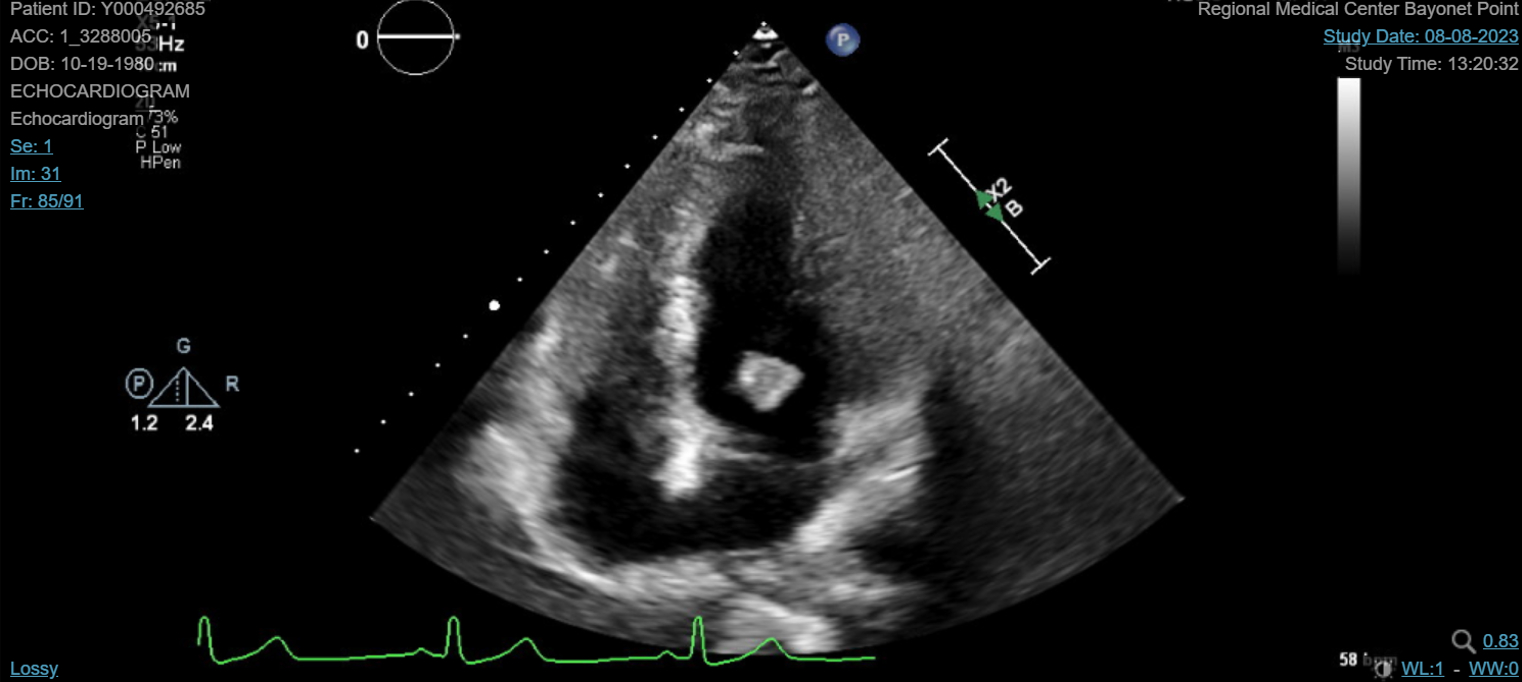

Abstract Body (Do not enter title and authors here): We describe a 42-year-old female with a past medical history significant for antiphospholipid syndrome (APS) who presented as a transfer to our facility for evaluation of stroke-like symptoms. She experienced acute onset dysarthria, left-sided weakness and a fixed rightward gaze preference. She was not a candidate for tenecteplase due to outpatient direct oral anticoagulant therapy. Computed tomography (CT) imaging of the head confirmed an acute infarct to the middle cerebral artery territory. She was taken for an emergent mechanical thrombectomy which she tolerated well. Repeat CT imaging ruled out hemorrhagic conversion. Transthoracic echocardiography revealed a 1.3 cm x 1.2 cm spherical mobile mass on the mitral valve, associated with a moderate to severe mitral regurgitation that was confirmed by transesophageal echocardiogram. The patient's respiratory status unfortunately declined and was consequently intubated. Blood cultures were negative and there was no history of intravenous drug use. The vegetation was considered marantic, representing nonbacterial thrombotic endocarditis (NBTE) secondary to APS and medication nonadherence. Cardiothoracic surgery offered surgical valve replacement after clinical recovery on an outpatient basis. She was subsequently extubated, transitioned to warfarin as recommended by hematology, weaned off supplemental oxygen, and discharged to inpatient rehab.